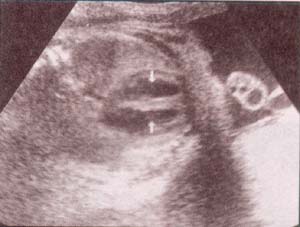

| fig 30. -(a). septum i-v. septum i-v. 32 semana | fig. 30.– (b). septum i-v íntegro entre las flechas. 35 semanas |